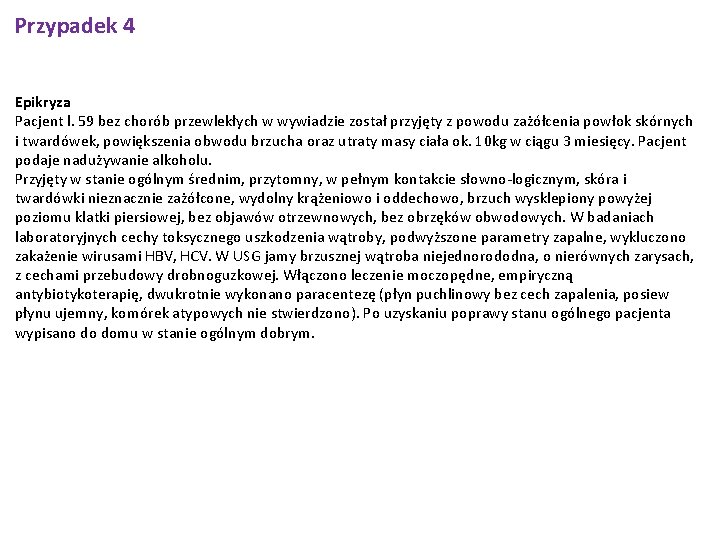

Przypadek 4 Epikryza Pacjent l. 59 bez chorób przewlekłych w wywiadzie został przyjęty z powodu zażółcenia powłok skórnych i twardówek, powiększenia obwodu brzucha oraz utraty masy ciała ok. 10 kg w ciągu 3 miesięcy. Pacjent podaje nadużywanie alkoholu. Przyjęty w stanie ogólnym średnim, przytomny, w pełnym kontakcie słowno-logicznym, skóra i twardówki nieznacznie zażółcone, wydolny krążeniowo i oddechowo, brzuch wysklepiony powyżej poziomu klatki piersiowej, bez objawów otrzewnowych, bez obrzęków obwodowych. W badaniach laboratoryjnych cechy toksycznego uszkodzenia wątroby, podwyższone parametry zapalne, wykluczono zakażenie wirusami HBV, HCV. W USG jamy brzusznej wątroba niejednorododna, o nierównych zarysach, z cechami przebudowy drobnoguzkowej. Włączono leczenie moczopędne, empiryczną antybiotykoterapię, dwukrotnie wykonano paracentezę (płyn puchlinowy bez cech zapalenia, posiew płynu ujemny, komórek atypowych nie stwierdzono). Po uzyskaniu poprawy stanu ogólnego pacjenta wypisano do domu w stanie ogólnym dobrym.